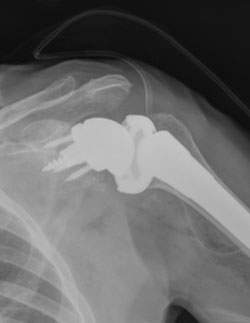

What type of implant is used for reverse shoulder replacement?

In a reverse shoulder replacement, the implant consists of two main components: The glenosphere and the humeral component.

- The glenosphere is the artificial ball component. It is made of metal – usually a metal alloy or titanium – and has a smooth surface to allow it to move freely. It replaces the damaged natural socket (glenoid) of the shoulder joint.

- The humeral component is the artificial socket. It is made of a durable plastic material called polyethylene. This component replaces the damaged natural ball – the humeral head (head of the humerus bone) – of the shoulder joint.

The materials used for the implant components are typically durable and biocompatible, meaning they are well-tolerated by the body and can withstand the stresses of everyday activities. Orthopedic surgeons choose the appropriate size and type of implant based on the patient's specific shoulder anatomy and the severity of their shoulder condition.